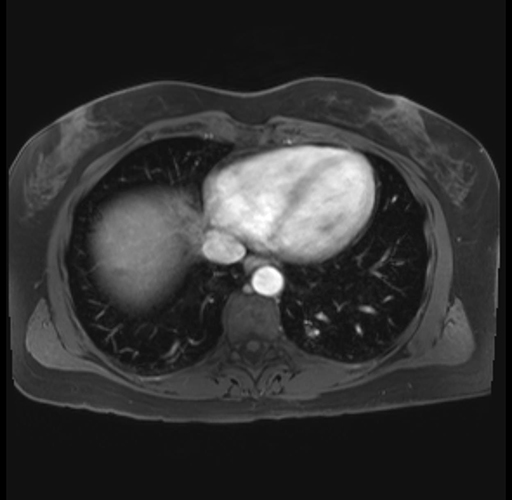

Imaging Analysis

Look through the patient's CT scan to identify any areas of concern for the necessary procedure.

Based on your CT findings, which issue(s) are present and would give reason for "planned slowing down moment(s)" in this case?

Considering a standard distal pancreatectomy procedure, what step(s) of the operation would you do differently in this case?